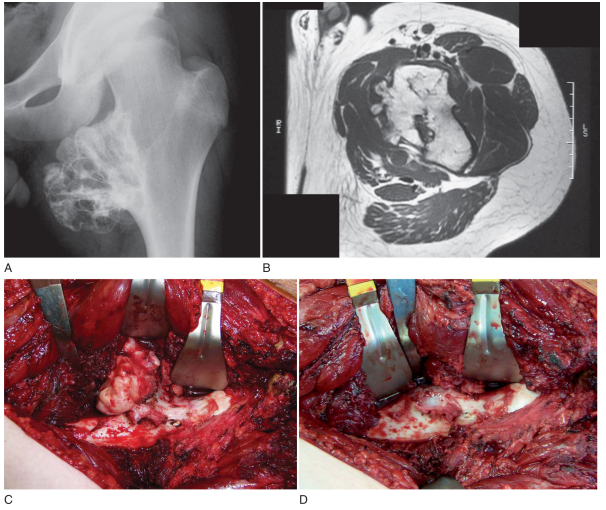

DEV HÜCRELİ TÜMÖR

Doktor Mehmet Subaşı

Sıklıkla 20-40 yaş arasında görülür, kadınlarda ise daha ...